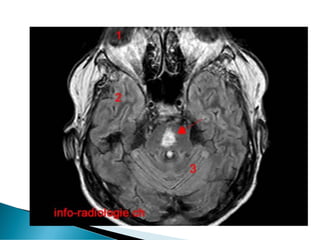

 Lésion cérébrale définitive si:

◦ Hyponatrémie chronique corrigée trop

rapidement(myélinolyse centro-pontine)

 Intervalle libre de 1 à 7 j après correction

 Somnolence, mutisme, dysarthrie,

quadriparésie spastique « Locked-in-

syndrome »

 Diag IRM retardé (1à plusieurs semaines)

 Favorisé par Cirrhose/ alcoolisme/grands

brulés/ dénutrition/ Hypoxie/hypokaliémie.